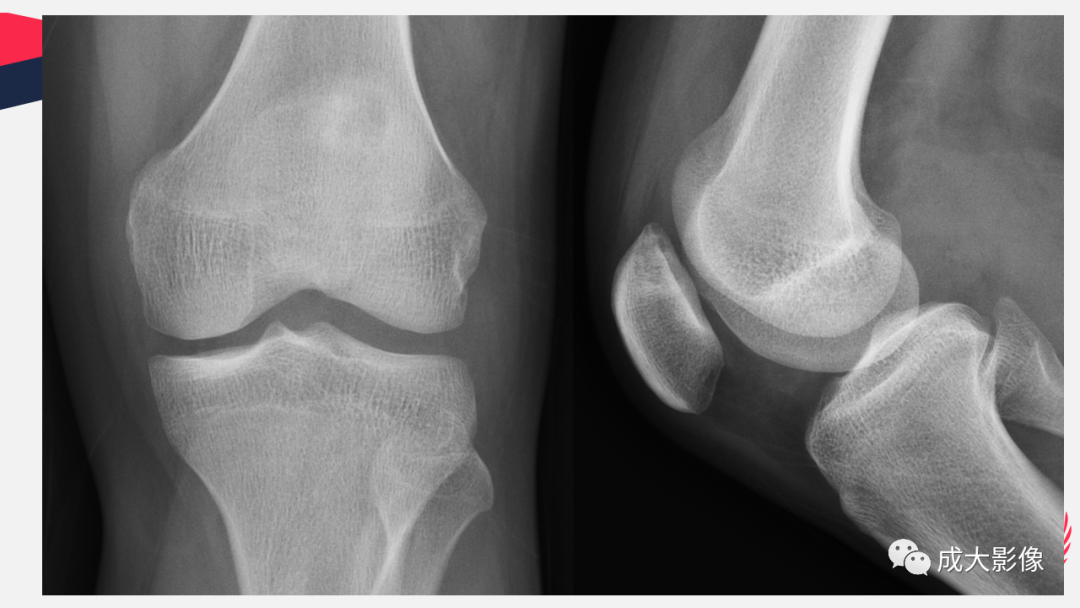

【PPT】剥脱性骨软骨炎-6

【PPT】剥脱性骨软骨炎-7